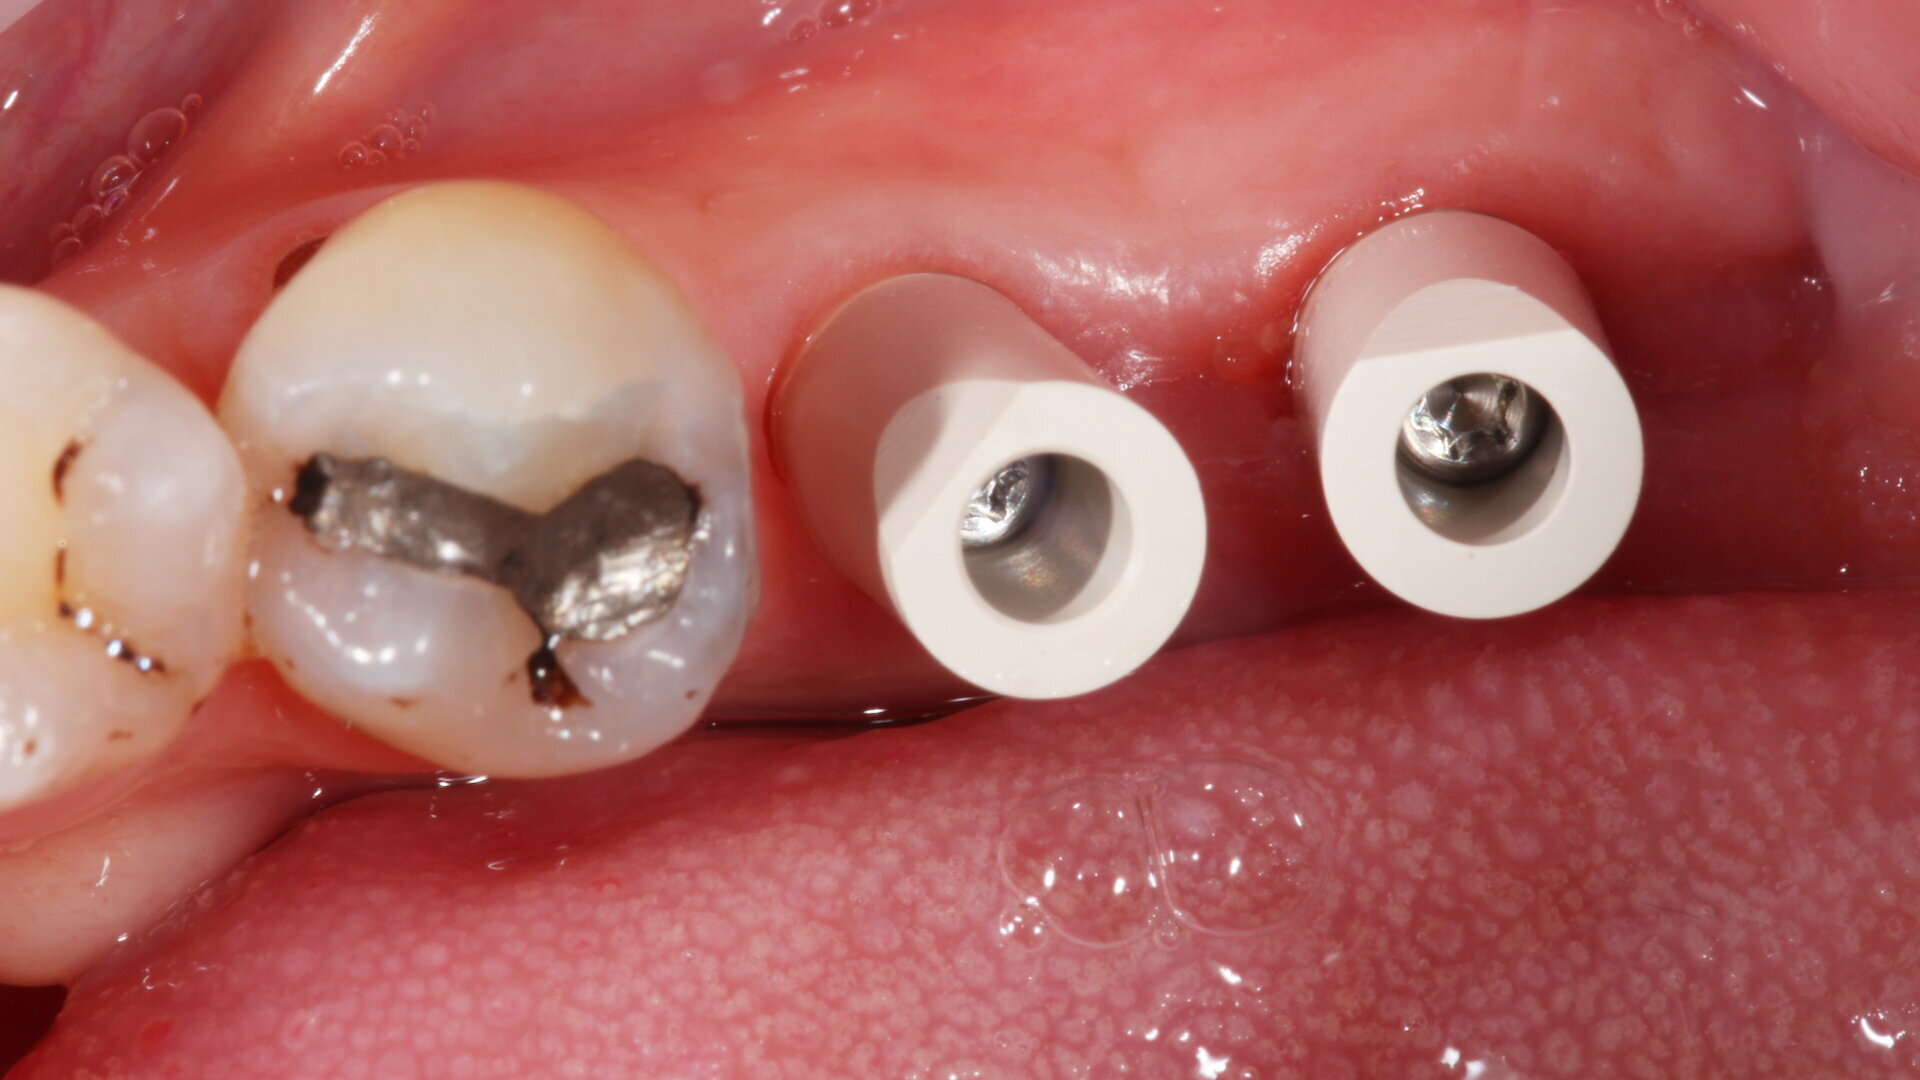

Fig. 9: Surgical placement of LL67 implants.

Fig. 11: Tissue level implants.

Once the implants are placed in situ and fully integrated, we then have a choice of conventional wet impression techniques versus digital intra-oral scanning. For the majority of cases, intra-oral scanning is extremely predictable and reliable—more so than conventional techniques—with milled (and lately printed) models having excellent properties and less accumulation of processing errors. However, deeply placed implants relative to adjacent teeth with deep contact points are very difficult to scan and pick up. Straumann tissue level implants offer a very straightforward restorative platform to scan from.